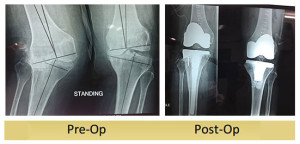

Total Knee Replacement : 60 years Old Lady

60 years old lady has been suffering from Rheumatoid arthritis for last 30 years. Both her knees got deformed and became painful because of Rheumatoid Arthritis. Her left knee became stiff in a bent posture as a result of which it would not touch the ground. She managed on the ... Read more..